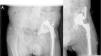

El promedio de seguimiento fue de 45,06 meses (12 a 73 meses), tiempo durante el cual no se ha producido ningún fracaso del Cup-Cage. Al final del seguimiento hubo 3 reintervenciones quirúrgicas (13,63%): un caso de infección, en el cual se practicó un desbridamiento y tratamiento antibiótico dirigido; un segundo caso se presentó con una luxación recidivante (2 episodios de luxación), y fue reintervenido mediante recambio del polietileno y cabeza femoral de mayor tamaño; y un tercer caso mostraba episodios repetidos de subluxación, sin ningún episodio de luxación completa, que precisó del recambio del polietileno y la cabeza debido a una mala orientación del mismo desde la cirugía inicial (fig. 5). No se practicó ninguna reintervención por aflojamiento o migración del sistema Cup-Cage.

En lo referente al control radiológico postoperatorio, en ningún caso se evidenció movilización de más de 5mm ni aflojamiento del Cup-Cage, obteniéndose la recuperación del centro de rotación con una reducción de la distancia vertical con la lágrima de 3,5cm a una media de 1,2cm. Encontramos un caso de osteólisis localizada alrededor de la inserción isquiática del Cup-Cage en el contexto de un recambio protésico por infección, sin progresión a lo largo del tiempo y sin traducción clínica. No encontramos ningún caso de rotura de tornillos o del implante (fig. 6).